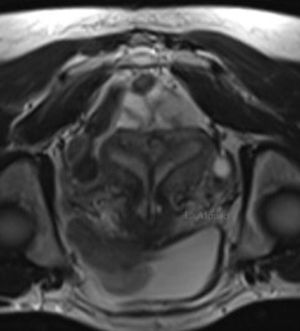

Hysteroscopic resection of the uterine septum improves fecundity of women with septate uterus and otherwise unexplained infertility